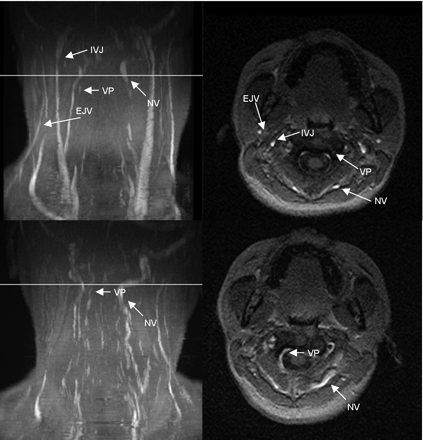

Table 1 shows the delineation of the IJV and collateral vessels in both positions. A great variability of the cerebral blood outflow tract was noted (Figs 1⇓⇓–4). In the supine position, additional vessels besides the IJV contributing to the cerebral venous outflow could be identified in all volunteers (Figs 1⇓⇓–4). The EJV was visible in 13 volunteers; the VP, in 5 volunteers; and the NV, in 7 volunteers.

MIP (left column) and axial source images at the level of C2 in supine (top row) and sitting positions (bottom row) in a healthy volunteer. In the supine position, there is a slight narrowing of the IJVs. The EJVs, the NV, and VP can be identified in the supine position. In the sitting position, IJVs and EJVs are no longer visible, whereas the NV are much more prominent. The VP can be identified.